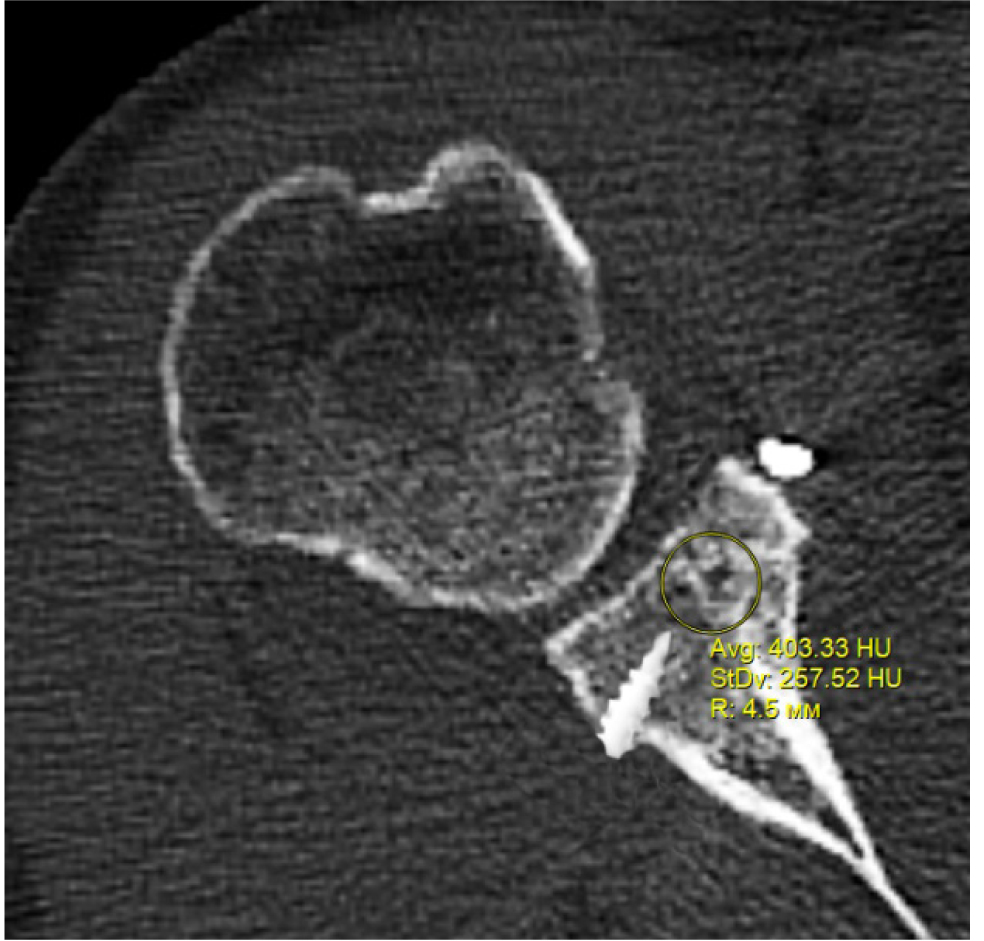

В программном обеспечении, на аксиальных КТ срезах оперированного плечевого сустава, выбирали инструмент «круг», который позволял посчитать среднюю плотность тканей внутри круга в единицах Хаунсфильда. Шкала единиц Хаунс-филда (HU) – шкалалинейного ослабления излучения по отношению к дистиллированной воде, рентгеновская плотность которой была принята за 0 HU (при стандартных давлении и температуре). Круг устанавливали таким образом, чтобы одна его половина была заполнена тканью гленоида, вторая половина тканью трансплантата (рис. 1–3). Оценивали плотность тканей над проксимальным винтом, между винтами, под дистальным винтом. Полученные данные анализировали с помощью пакета Microsoft Excel.

Рис. 2. Оценка плотности ткани между винтами